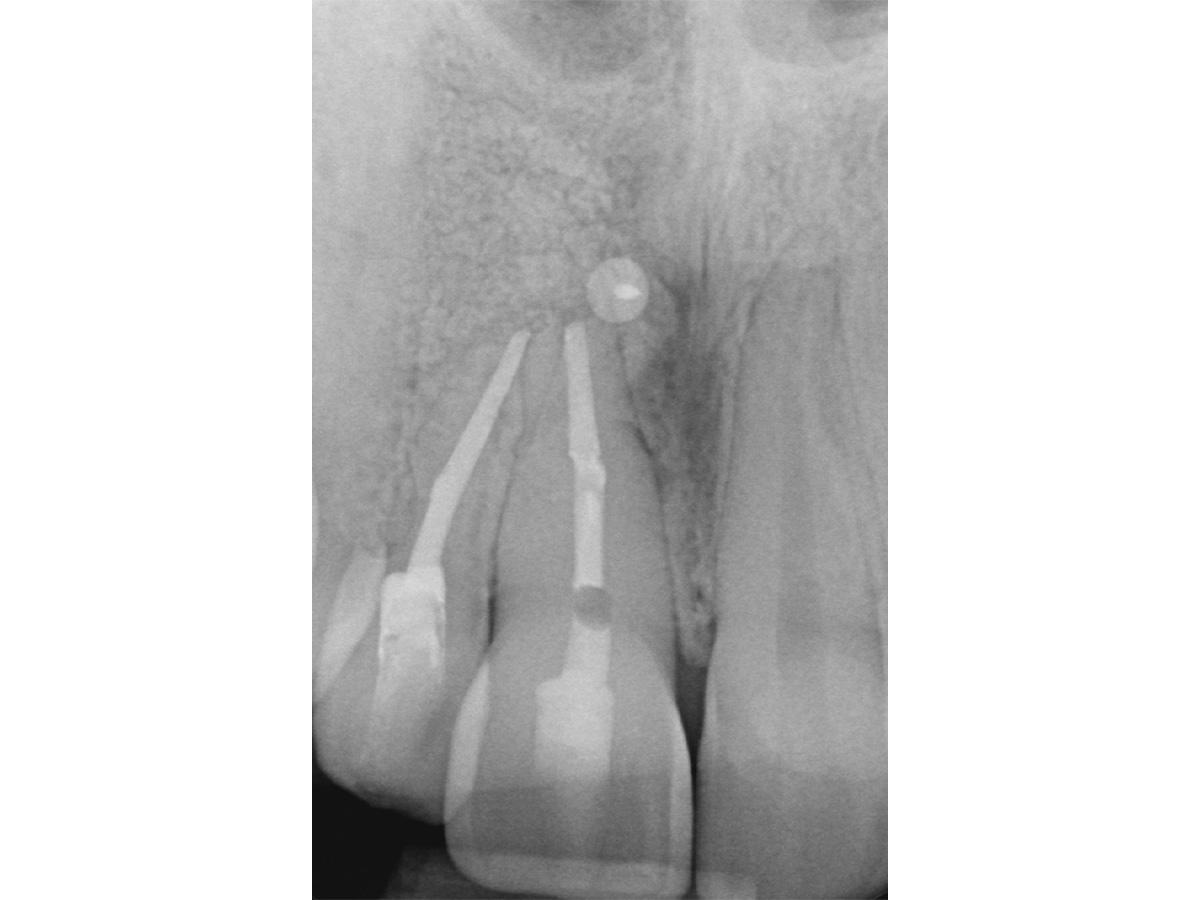

Abbildung 4

Prä-OP: Das OPG zeigt eine Erhellung im Knochenbereich regio 11 und 12.

Nach einem Zahntrauma im Jugendalter mit anschließender endodontischer Versorgung stellte sich unsere 24-jährige Patientin mit seit einigen Monaten bestehendem, rezidivierendem Druckgefühl und leichten Schmerzen in regio 11 und 12 vor (Abb. 1, 2, 3). Die klinische Untersuchung ergab an Zahn 11 und 12 Lockerungsgrad 1 und, wie zu erwarten, eine negative Sensitivität. Es lag ein leichter Perkussionsschmerz vertikal wie horizontal vor. Die Krone auf Position 11 zeigte eine leichte Verfärbung im Vergleich zu den Nachbarzähnen. Ein OPG ergab eine – in ihrer Ausdehnung nicht sicher zu beurteilende – Aufhellung im Knochenbereich regio 11 und 12 (Abb. 4). Als Nebenbefund waren teilretinierte Zähne 38 und 48 sowie ein vollständig retinierter Zahn 28 als Mikroform nachzuweisen. Ein zusätzlich durchgeführtes DVT zeigte eine große zystische Formation unter Einschluss der Wurzeln 11 und 12, die vom Canalis nasopalatinus bis mesial 13 mit einer kleineren Perforation zum Nasenboden und größeren Perforationen nach vestibulär und palatinal reichte (Abb. 5, 6, 7).